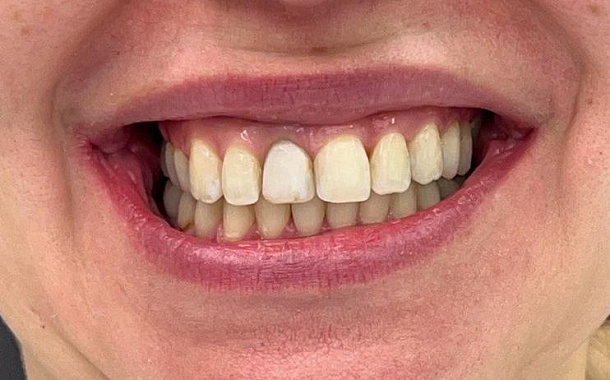

- Визуализация результатов: Пациенты могут увидеть предполагаемый результат лечения еще до его начала, что помогает в принятии информированных решений.

- Максимально точные и эстетичные ортопедические конструкции